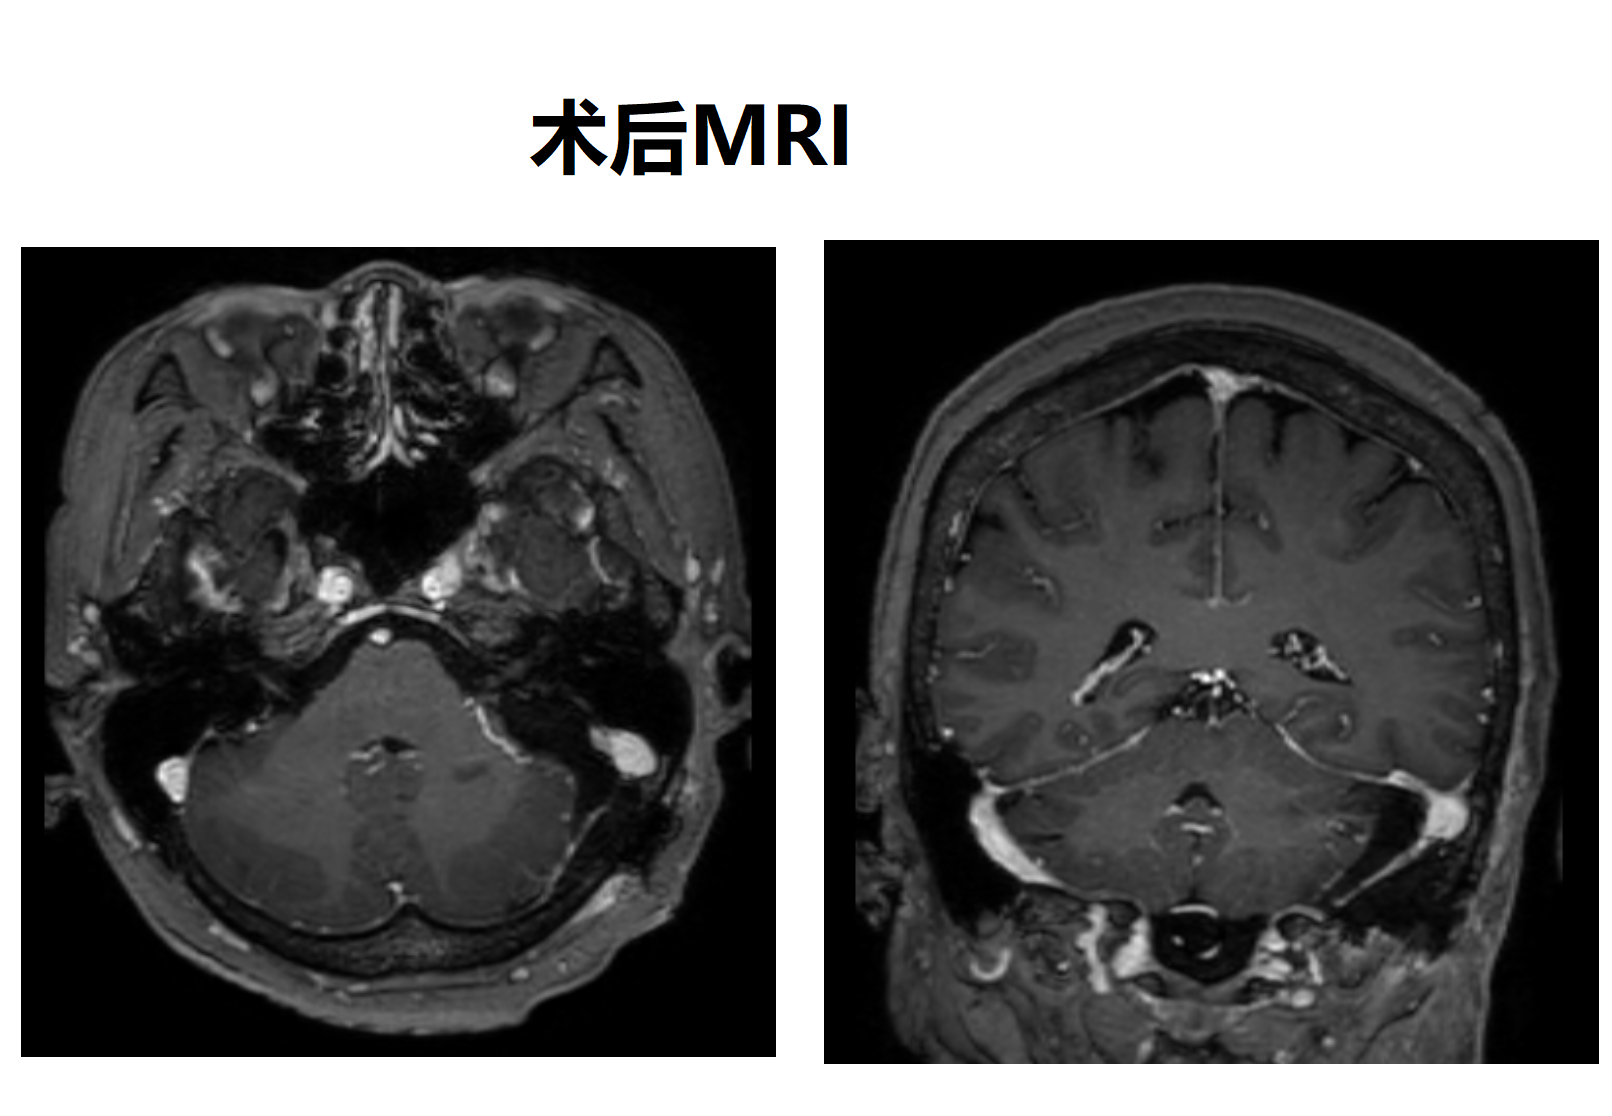

采用C形切口,打开硬膜即可见肿瘤位于横乙角,基底附着于岩骨侧壁 以及 小脑幕,肿瘤与小脑有明显分界,易于分离。肿瘤全切后可见面听神经、后组颅神经表面的蛛网膜界面完整。属于蛛网膜外完整切除肿瘤。全程监测Ⅴ-Ⅶ-Ⅹ-Ⅺ颅神经自由肌电图。术后患者无相关并发症。